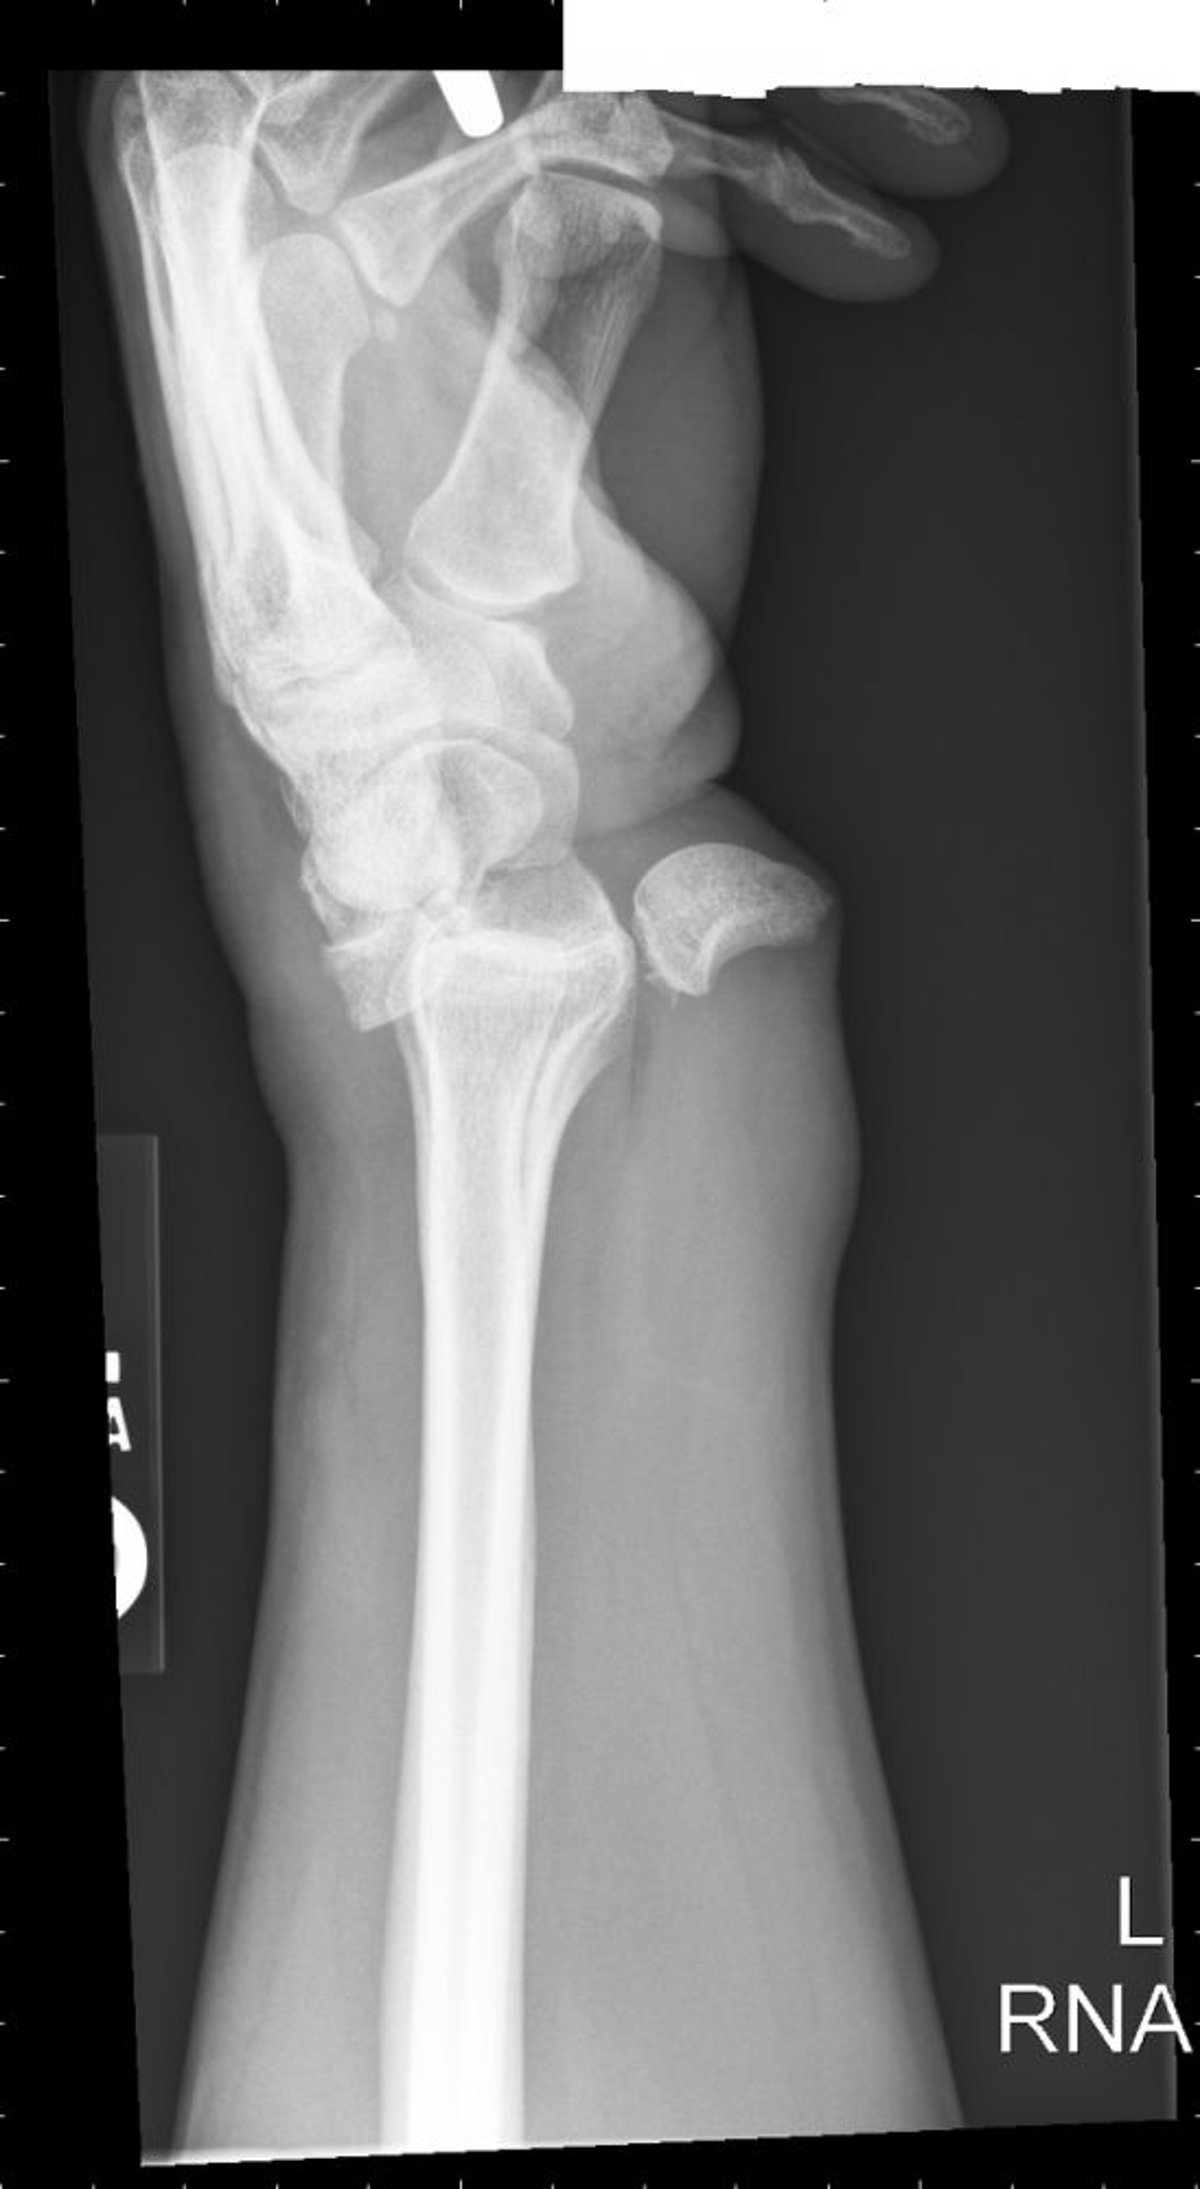

Вывих полулунной кости

Вывих полулунной кости приводит к тому, что конфигурация этой кости приобретает вид «опрокинутой чайной чашки».

Image courtesy of Danielle Campagne, MD.